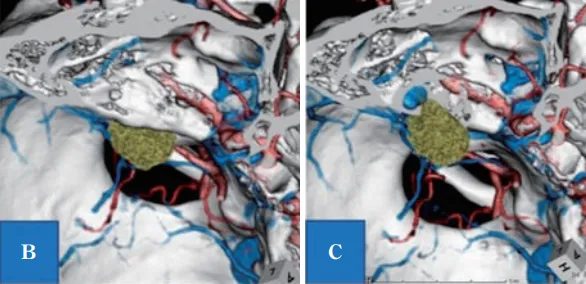

(图1)根据影像学检查结果诊断为听神经瘤,术前头部计算机断层扫描血管造影(CTA)观察到在内耳道壁后方形成的颈静脉球(带骨图像)。

图1B:计算机断层扫描-骨骼血管造影(CTA)显示,左上前侧有肿瘤(绿色肿块是增强区域);C:B所示的IAC壁骨缺失,显示颈高球非常靠近内听道和肿瘤。